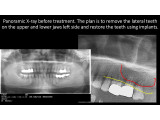

Direct implantation with immediate loading & FOLLOW-UP 7 YEARS AFTER SURGERY

Clinical case: Direct implantation with immediate loading, bone augmentation, sinus lifting and soft tissue monitoring. Follow-up 7 years after surgery

Dentist: DDS PhD Ilia Mushayev/Sidhedent, DMi (Israel)